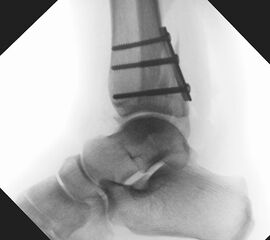

Liegt eine Fraktur des oberen Sprunggelenks vor, ist sowohl zur Entscheidung für ein konservatives oder operatives Vorgehen, als auch zur Operationsplanung, ein ausreichendes Verständnis der Fraktur und ihrer Morphologie notwendig. Insbesondere bei komplexen Verletzungen ist dafür die konventionelle Röntgenaufnahme in vielen Fällen nicht ausreichend. So konnten z.B. Black et al. zeigen, dass die operative Strategie zur Versorgung von OSG-Frakturen in 24% basierend auf einer zusätzlichen CT-Bildgebung relevant geändert wurden 7. Dies betraf die Lagerung, die Wahl des Zuganges und die Art der osteosynthetischen Versorgung. Besonders häufig änderte sich das Vorgehen bei Verletzungen des medialen (21%) und des posterioren Malleolus (15%). Darüber hinaus führten dislozierte (dislozierte Frakturen 31% vs. nicht-dislozierte Frakturen 20%) oder komplexe Frakturen (Trimalleolar-Frakturen 29% vs. Unimalleolar-Frakturen 10%) besonders häufig zu relevanten Änderungen des operativen Vorgehens. Die Computertomographie ist daher, insbesondere bei Bi- und Trimalleolar-Frakturen, essentiell für das Verständnis der Fraktur und somit für die Planung und Durchführung der Operation. In Abbildung 4 und 5 sind exemplarisch ein Röntgen- und ein CT Befund gegenübergestellt.